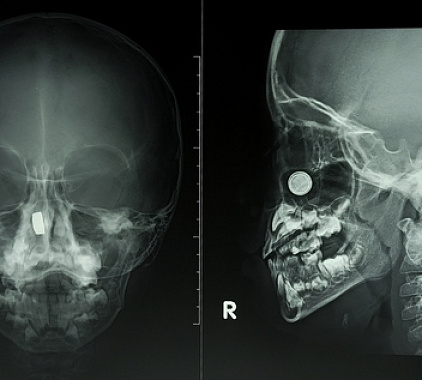

- Рентген носоглотки в боковой проекции. Голова слегка поворачивается, чтобы луч прошел сбоку. Такая проекция лучше всего показывает высоту носоглоточного свода, размеры аденоидов, степень перекрытия хоан, дает оценку просвета носоглотки. Именно боковая позиция помогает визуализировать те самые «тени», которые мешают воздуху проходить.

- По Колдуэллу. Пациента просят наклонить лоб к кассете под углом. Проекция по Колдуэллу улучшает видимость лобных пазух и решетчатого лабиринта, а также их соотношение с областью носоглотки. Полезна, когда врач подозревает комбинированный процесс и хочет оценить верхние отделы носа.

- По Уотерсу. Здесь упор делается на верхнечелюстные пазухи и дно орбит. Положение головы с подбородком у кассеты смещает проекцию так, чтобы придаточные пазухи четче отделялись от костных перегородок, а переход к носоглотке просматривался более свободно. Этот вариант часто добавляют к боковой проекции для комплексной картины.

- Аденоидные разрастания. Утолщенная тень в своде носоглотки, перекрывающая просвет частично или значительно. По рентгенограмме судят о степени, врач сопоставляет с жалобами.

- Синусит. Уровень жидкости или диффузное «затемнение» в пазухах на фоне отека; на снимке по Уотерсу эту зону будет видно лучше.

- Искривление перегородки. Косвенные признаки — асимметрия носовой полости, смещение костных контуров.

- Травма. Линии перелома костей носа/скул/стенок синусов, подвывихи, участки смещения. В экстренной ситуации это помогает быстро отправить пациента к профильному специалисту.

- Опухолевые образования и кисты. Описывают как «объемные тени», уточняют границы и влияние на окружающие структуры; далее решают вопрос о КТ/МРТ.

- Гипертрофия мягких тканей. Утолщение в области носоглоточной миндалины, рыхлые тени вдоль задней стенки — косвенные признаки воспаления.

Важно понимать: рентген — базовый визуальный метод. Он отлично позволяет увидеть кости и «крупные» изменения мягких тканей, но не дает срезов, как КТ. Поэтому в сложных случаях врач дополнит диагностику другими исследованиями, чтобы оценить состояние в деталях.